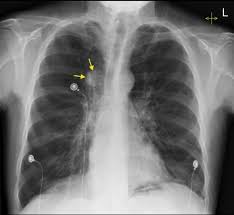

Research shows obesity raises the risk of heart disease.

Read more: Research shows obesity raises the risk of heart disease.Source: Virginia Tech Mark Renton, a postdoctoral associate with the Fralin Biomedical Research Institute at VTC, will investigate how the pannexin-1 protein regulates blood flow in an obesity-induced heart condition. Health & Wellness At home in Australia, Mark Renton started playing football as soon as he could. He figured it would eventually lead to a…